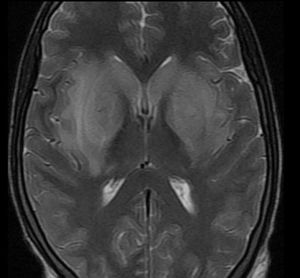

30 y old young man in coma GCS 7/15 febrile with convulsions and irritability post animal bites Is the MRI help you to reach the diagnosis?!

Rabies ??